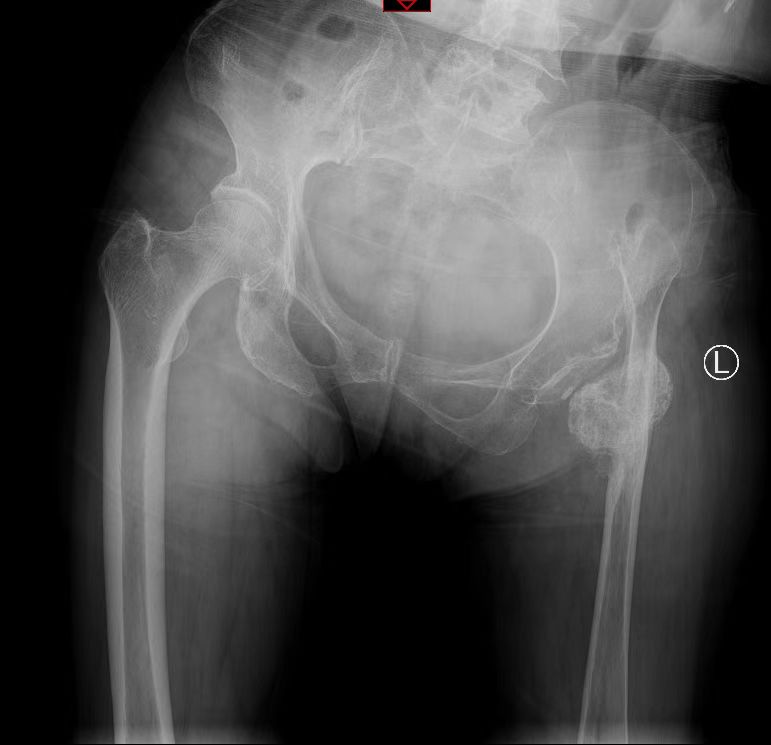

“腿疼治了一辈子,花了几万块钱也没治好,到了正骨医院才找到病根……”家住巩义的吕阿姨说起辛酸的往事,不禁红了双眼。现年74岁的吕阿姨,朦胧的回忆中依稀记得“应该是6岁摔伤了左髋”,自幼便出现瘸腿走路,在缺医少药的年代,忍受了60余年的痛苦。

2022年3月,吕阿姨在家人的鼓励下就诊于我院髋关节外二科,由于复杂的病情,李红军主任团队为她量身定制了手术方案,经过医患双方的共同努力,吕阿姨获得了良好的生活质量。“因为身体的残疾,在社会上经常会遭受别人异样的目光,心理很自卑,现在终于过上了正常人的生活!”吕阿姨兴奋的说。